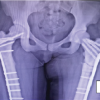

The MRI showed a solitary lesion in the proximal right femoral metaphysis extending into the femoral epiphysis superiorly and inferiorly to the subtrochanteric level. There was a homogenous appearance on T1-weighted images with a hyperintense signal on T2-weighted images. The main differential diagnoses were GCT, chondroblastoma, and a primary malignant lesion. The patients hip was reconstructed with a hybrid THA (Fig. 4) as the local cauterizing effect of the femoral bone cement has been known to reduce the incidence of local recurrence [7,8]. Bone samples were sent for the histopathology.